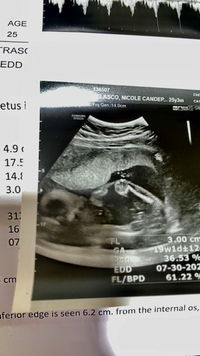

Mommy of Kiva